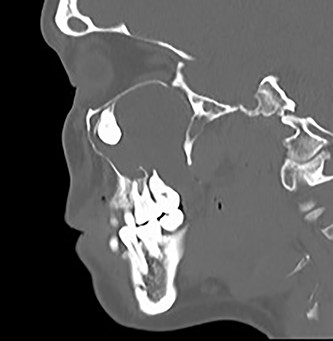

Sagittal CT image of the right ectopic tooth at the antrum of the right maxillary sinus.